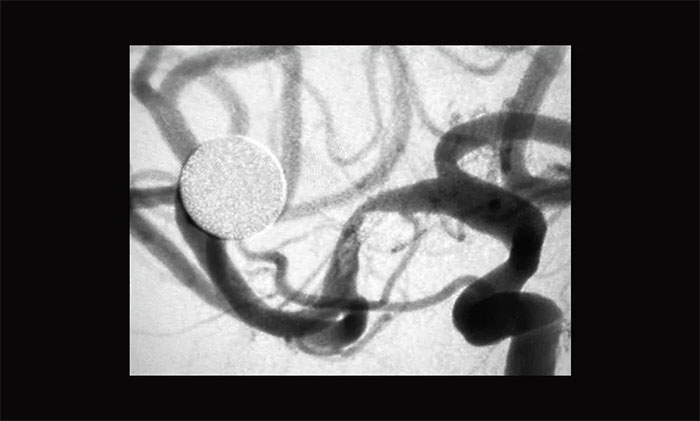

术中,经右侧桡动脉穿刺行全脑血管造影可见,右侧大脑中动脉MI段重度狭窄,约90%,远端血流缓慢,左侧椎动脉起始段迂曲,基底动脉冗扩。考虑患者反复出现脑梗死与右侧大脑中动脉狭窄有关,且其它血管对右侧大脑中动脉供血区域基本无代偿,一旦发生大脑中动脉闭塞将发生严重后果。遂决定行右侧大脑中动脉M1段球囊扩张术及取栓术。

患者血管迂曲,张琪博士在周林华医生协助下,经过多次尝试后,微导管、微导丝终于成功到达狭窄部位,顺利进行球囊扩张并以支架拉栓,30分钟后再次行造影提示右侧大脑中动脉M1段无明显改善,遂决定行右侧大脑中动脉支架置入术。

▲ 术前DSA影像:右侧大脑中动脉MI段重度狭窄